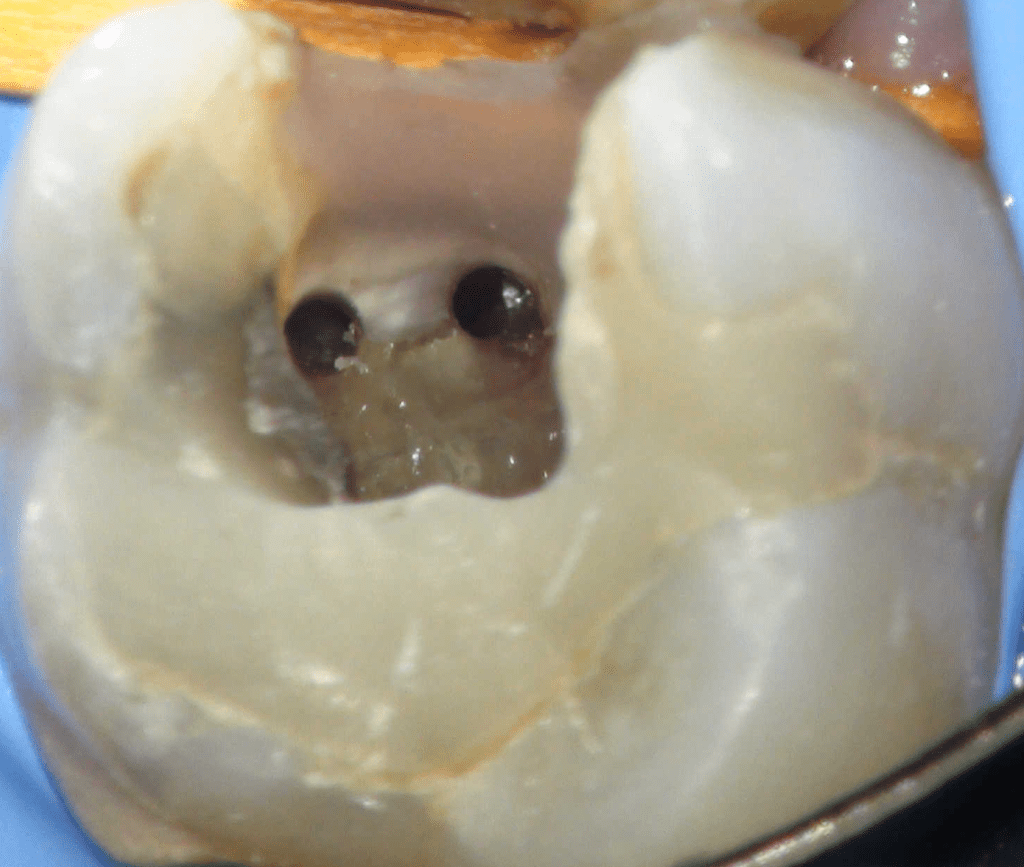

Reco preendo + 4 conductos molar superior

Reco preendo, 2o Molar superior